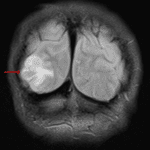

- Cortically-based T2/FLAIR hyperintense lesion in the right occipital lobe

- Associated solid nodular enhancement measuring 15 mm with corresponding mild restricted diffusion

- Overlying calvarial scalloping

- Mild local mass effect without midline shift or evidence of herniation or hydrocephalus

Ganglioglioma